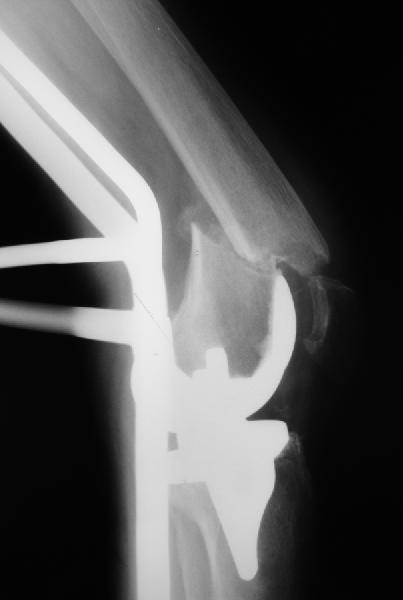

Уважаемый, Игорь! То что демонсрирует Александр Николаевич, высший пилотаж "neilinga" В нашей стране выполяется единичными спциалистами. Поэтому если не владеете методикой лучше пригласить к себе Челнокова. в случае накостного остеосинтеза, за который говорит ожирение и сопутствующая патология, не используте пластину Рыбинска. она не правильно предмоделирована и невесть из какого металла выполнена.поэтому неизвестно когда сломается при осевой нагрузке, и, кроме того,вы заведомо создадите вальгусную дефомацию, что повлечет за собой расшатывание компонентов. оптимальна в данном случае пластина "Synthes" скоминированными отверстиями. точно титан, идеально предмоделироана, винты надежно блокируются в отверстиях в отличие от Рыбинска.оперировать необходимо на спицевом дистракторе, спицы проводить перпендикулярно оси отломков. после репозиции под онтролем ЭОП чере два доступа пластину максимальной длины.дистальн заблокировать не менее 6 отверстий, проксимально-5.если нет возможности выполнить предложнные варианты, лучше пациентку перевести в отделение высшего уровня.Слишком высоки ставки. С уважением, Сергей.